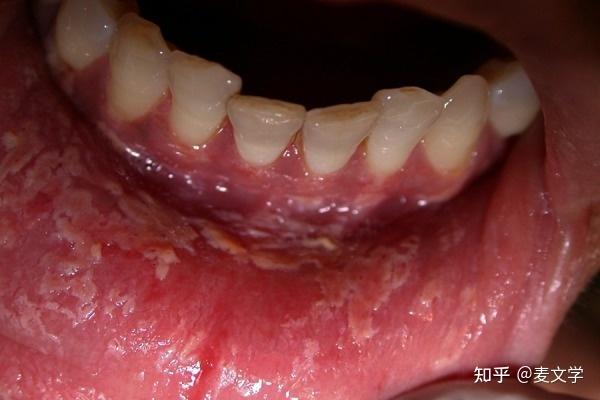

(图片来源网络,侵删)

- 自行更换和调整后,症状持续不缓解或加重。

- 口腔内膜脱落范围大、疼痛剧烈,影响进食和说话。

- 脱落处出现白色、条纹状或溃烂的斑块,长期不愈合。

- 伴有发烧、淋巴结肿大等全身症状。

医生会检查您的口腔,排除其他疾病(如扁平苔藓、天疱疮、白斑病等),并给出专业的治疗方案。